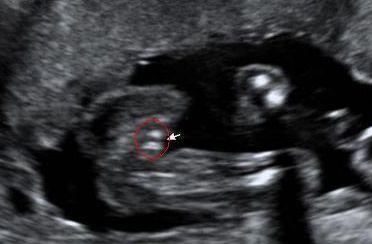

在12周的时候,宝宝的身长大约有6厘米左右,体重也在不断增长。这时候,宝宝的头部和身体的比例开始逐渐协调,四肢也开始变得更有力。你会发现,宝宝的手指和脚趾已经清晰可见,而且手指关节也开始形成。

12周的胎儿视频还会让你看到宝宝的脸部特征。这时候,宝宝的眼睛已经从侧面移到了正面,耳朵也变得更加清晰。虽然宝宝的眼睛还是闭着的,但你可以看到眼皮和眼睑的轮廓。

12周胎儿视频是通过超声波技术拍摄的。超声波技术是一种非侵入性的检查方法,可以安全地观察宝宝在妈妈肚子里的情况。